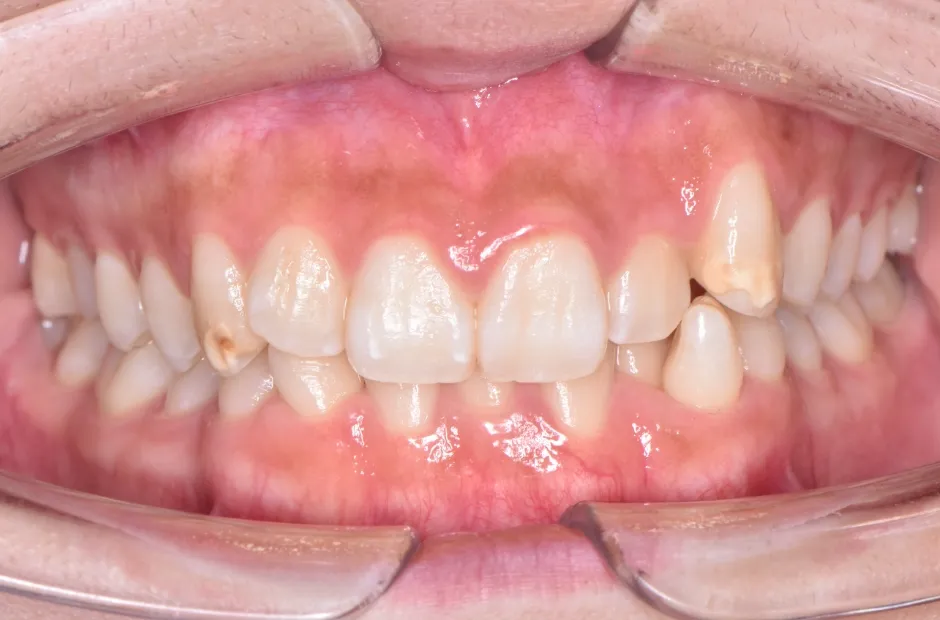

八重歯・でこぼこ・乱ぐい歯

(叢生)

歯が並ぶスペースが足りないために、歯が重なったり前後にずれて生えていたりする状態です。犬歯(八重歯)など目立つ部分の歯列が乱れている場合は、口元の印象に悪影響を与えます。原因としては、遺伝や乳歯の早期抜歯、顎の成長不足などがあげられます。歯磨きが不十分になりやすく、虫歯や歯周病のリスクが高まりやすい不正咬合です。矯正治療を受けると、見た目がよくなるだけでなく清掃性が高まり、お口の健康を維持しやすくなります。

叢生

| 診断名・主訴 | 叢生 |

|---|---|

| 年齢・性別 | 43歳・女性 |

| 治療期間・回数 | 2年7か月 27回 |

| 治療に用いた主な装置 | 舌側矯正 |

| 抜歯部位 | 両顎4,4 |

| 治療費 | 100万円(税抜) |

| リスク・副作用 | 装置による違和感・疼痛・歯肉退縮・歯根吸収・虫歯のリスクなど |

治療前